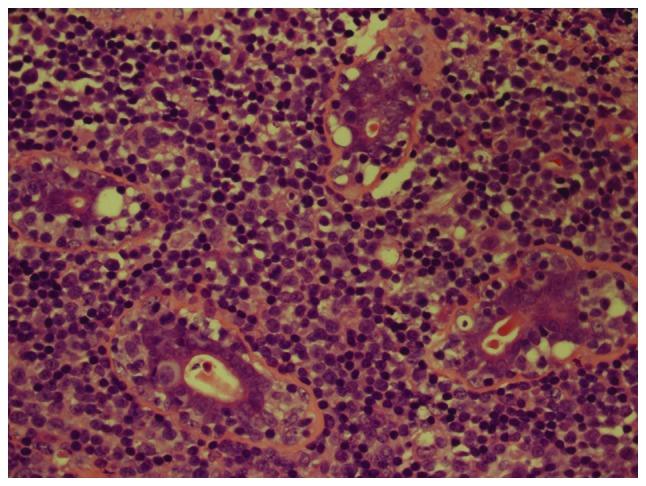

The current study presents a case of primary T-cell lymphoma (PTBL), unspecified, in a 27-year-old female. The patient received chemotherapy [cyclophosphamide, epirubicin, vindesine and prednisolone (CHOP) and VP-16 plus CHOP (ECHOP)] and autologous peripheral blood stem cell transplantation, however, relapse occurred rapidly. The recurrent tumor exhibited increased levels of karyopyknosis and nuclear fragmentation and a higher Ki67 index compared with the primary tumor. No response to subsequent chemotherapy, including ECHOP and gemcitabine, dexamethasone and cisplatin, was observed. The patient succumbed to PTBL, unspecified, 18 months after the diagnosis. We hypothesize that autologous peripheral blood stem cell transplantation is ineffective for PTBL.

本研究报告了一例27岁女性的原发性未特定类型T细胞淋巴瘤(PTBL)病例。该患者接受了化疗[环磷酰胺、表柔比星、长春地辛和泼尼松龙(CHOP)以及VP - 16加CHOP(ECHOP)]和自体外周血干细胞移植,然而,疾病迅速复发。与原发性肿瘤相比,复发性肿瘤显示核固缩和核碎裂水平增加,且Ki67指数更高。未观察到对后续化疗(包括ECHOP以及吉西他滨、地塞米松和顺铂)的反应。该患者在诊断后18个月死于原发性未特定类型T细胞淋巴瘤。我们推测自体外周血干细胞移植对PTBL无效。